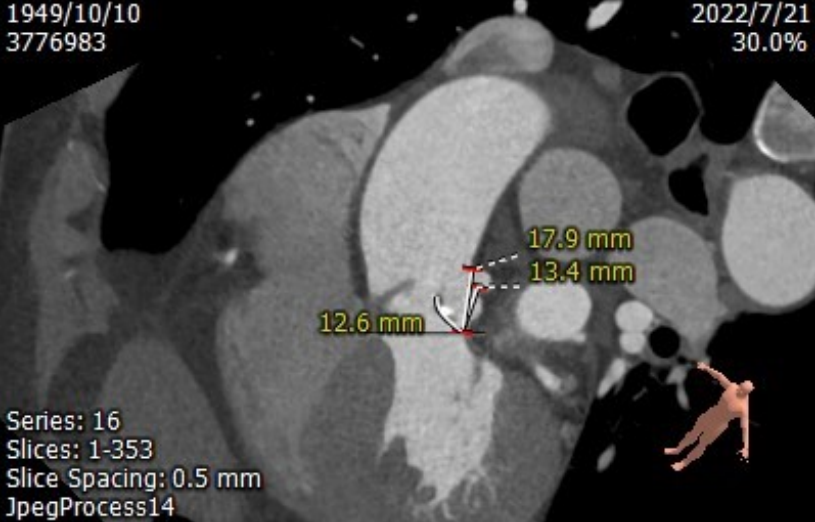

CT测量

主动脉根部CT测量

左室流出道周长:71.5mm

瓣环周长:72.1mm

横心位:58°

升主动脉扩张,周长:139.7mm

右冠高度:13.3mm;瓣叶长度:14.4mm

左冠高度:13.4mm;瓣叶长度:12.6mm